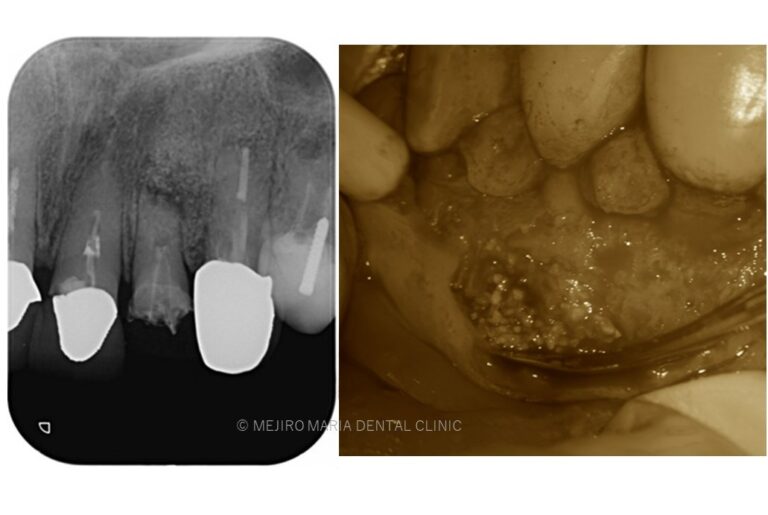

• 【症例】根尖部に充填された人工骨が感染し根尖性歯周炎が難治化した症例。精密根管治療でのリカバリー

• 【症例】歯根端切除術(意図的再植術)により、病変の大きい根尖性歯周炎の抜歯を回避